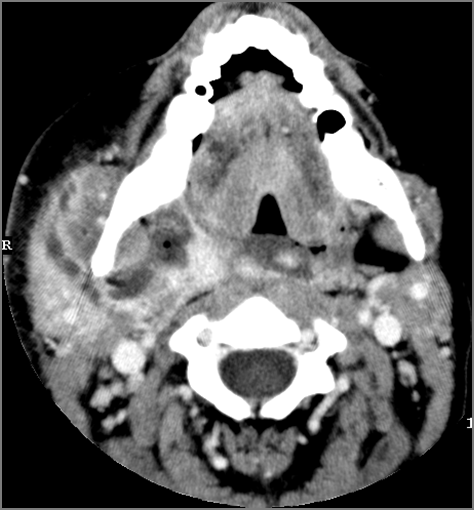

There is excessive enhancement or thickening of the mucosa or hypertrophy of the pharyngeal, palatine or lingual tonsillar tissue or the lymphoid tissue along the glossotonsillar sulci and posterior pharyngeal wall. [Yes/No]

There is an abscess relatively centrally within the lymphoid tissue of the palatine tonsil. [Yes/No]

There is evidence of a developing abscess at the periphery of the lymphoid tissue of the palatine tonsil within the potential peritonsillar space. [Yes/No]